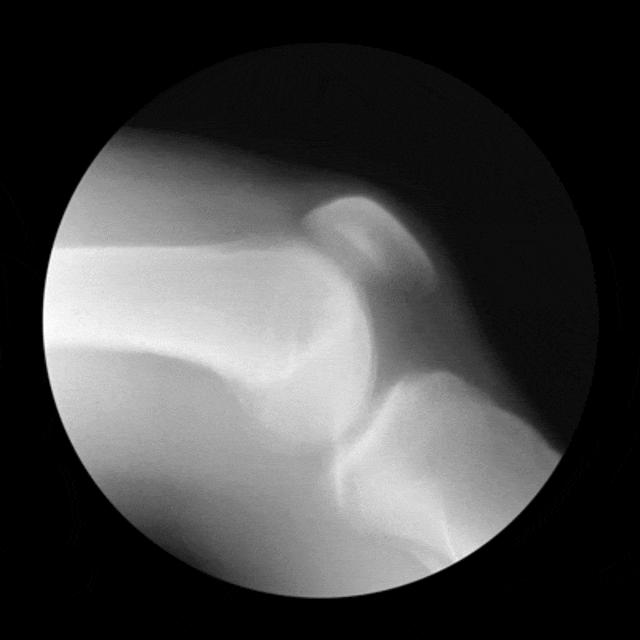

膝关节软骨损伤分为两大类:慢性磨损退变以及急性外伤导致的软骨剥落。

慢性软骨磨损退变往往是由髌骨关节、股骨髁软骨磨损引起的,是骨关节炎的早期表现。

患者常表现为关节酸痛、局部压痛、上下楼梯痛、膝内侧酸痛等。症状会随着时间的推移而逐渐加重,患者出现久坐后站不起来,变天时膝关节不适,活动后有所缓解,但是活动久了又出现不适。